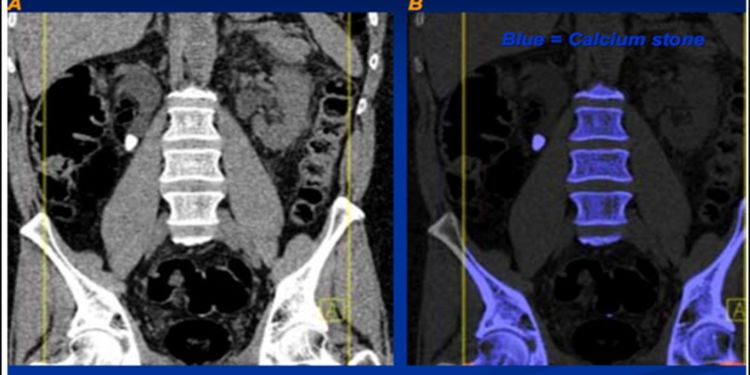

Scope: JRNM covers a wide range of topics related to radiation and nuclear medicine, including but not limited to:

- Diagnostic and therapeutic applications of nuclear medicine, Radiopharmaceuticals and their development

- Radiation therapy techniques and technologies, Imaging modalities such as PET, SPECT, and molecular imaging